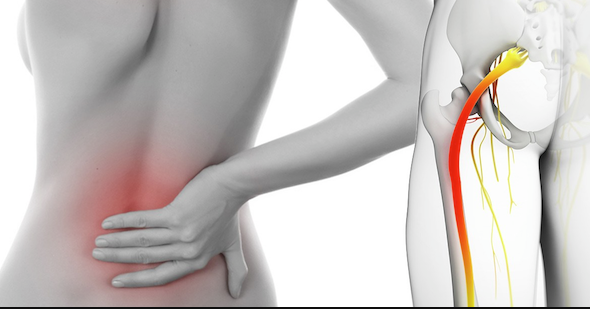

Išijas nije prava medicinska dijagnoza, ali je jedan od najčešćih problema sa leđima u današnje vrijeme. Osim jakog bola, mnogi ljudi osjećaju utrnulost, peckanje ili slabost u nogama, što može značajno otežati svakodnevni život.

Bol koji počinje u donjem dijelu leđa ili kuku i širi se niz nogu.